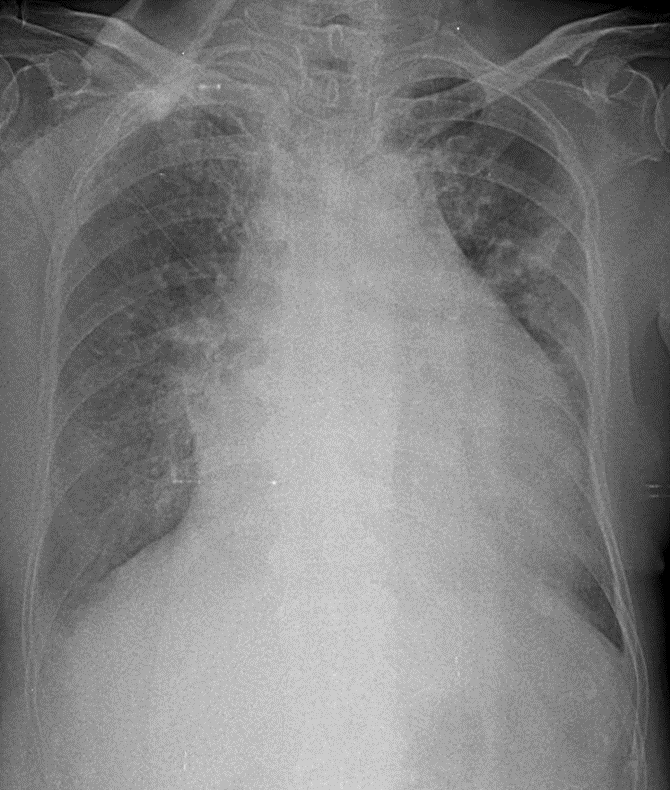

Hãy phân tích tình huống nữ 80 tuổi

1-Thâm nhiểm mô kẻ rải rác hai phổi => Viêm phổi 2-Bóng tim to toàn bộ